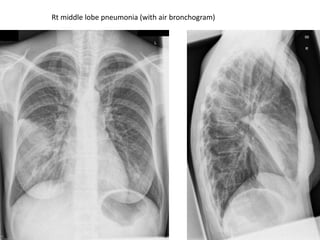

Rt middle lobe pneumonia (with air bronchogram)

•CHEST X-RAY Consolidation (homogenous opacification in a lobar pattern).

•Air bronchogram

•No volume loss

•Atelectasis (small airway obstruction)

•CT SCAN FOCAL GROUND GLASS OPACITY / dense opacification of the entire lobe

•COMPLICATIONS PARA-PNEUMONIC EFFUSION , EMPYMA